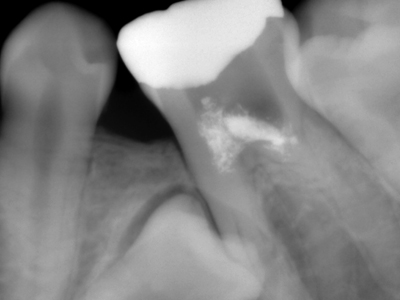

2. 初診時右下6番X線デンタル

初診時の主訴であった右下6番の歯冠が脱離した部位のX線デンタルです。患者様は銀歯が脱離してしばらく放置したとのことで、痛みもないので又歯冠をつければ良い位に考えていた様子でした。歯根吸収の状況より当時22歳とのことで、相当若年時に抜髄されたのが想像できます。考えてみれば6歳に萌出して15年で抜歯となった訳です。上顎8番の同部への移植も考慮しましたが断念しました。